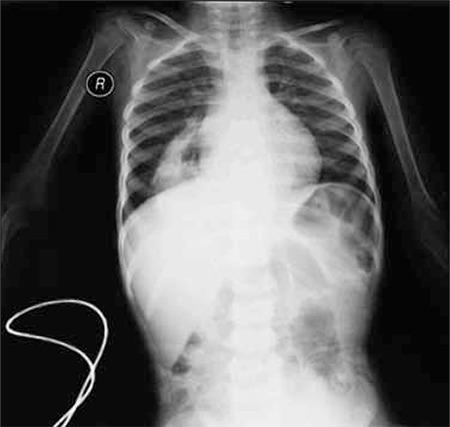

Severe iron deficiency anemia due to late presentation of congenital diaphragmatic hernia in a toddler.

https://cdn.ncbi.nlm.nih.gov/pmc/blobs/6b84/3781611/17946a6979fa/TJH-29-430-g1.jpg